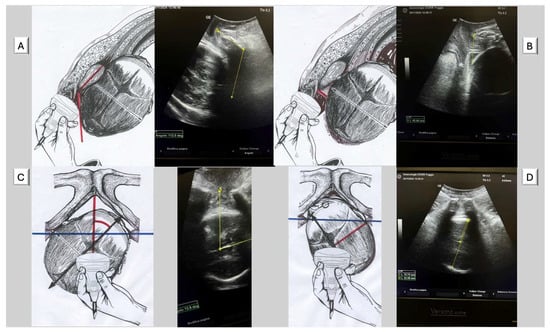

The four geometric parameters measured in AIDA (Figure 2) offered potential explanations for the high cesarean rates observed in certain Robson groups. (A) Angle of Progression (AoP): This parameter can identify cases with inadequate fetal descent despite apparently normal labor progress by clinical assessment. This parameter was particularly valuable for objectively assessing station, which traditionally relied on subjective vaginal examination. Studies demonstrated that AoP < 110° was associated with an increased risk of cesarean delivery. (B) Head–Symphysis Distance (HSD): This parameter can provide objective measurement of station and descent, potentially explaining failure to progress in the second stage. HSD > 25 mm indicated that the fetal head remained high in the pelvis despite apparent progress by clinical assessment. (C) Midline Angle (MLA): This parameter can identify cases where incomplete rotation impeded vaginal delivery. MLA > 45° suggested malrotation that could significantly complicate vaginal delivery, particularly in nulliparous women with induced labor. (D). Asynclitism Degree (AD): This parameter can explain cases of labor dystocia related to unfavorable fetal head position that would not be apparent on routine clinical examination. Significant asynclitism (AD > 7.0 mm) prevented optimal interaction between the fetal head and maternal pelvis, impeding descent and rotation. Malvasi et al. found that severe asynclitism was strongly associated with cesarean delivery regardless of other parameters, suggesting it might be a key factor in dystocic labor.

Figure 2. The figures illustrate the four parameters of A.I.D.A during the prolonged second stage of labor in Occiput Posterior Position. (A) Angle of progression (AoP): the drawing on the right (red angle) and the US photo on the left show the AoP with the fetal head in Occiput Posterior Position (O.P.P.) (yellow angle); (B) fetal head–symphysis distance (HSD): the drawing on the right (red line) and the US photo on the left show the HSD (yellow line) with the fetal head in Occiput Posterior Position (O.P.P.); (C) midline angle (MLA): the drawing on the right (red angle) and the US photo on the left (yellow angle) shows the MLA with the fetal head in the Left Occiput Posterior Position (L.O.P.P.); (D) asynclitism degree (AD): the drawing on the right (red line) and the US photo on the left (yellow short line) show the AD with the fetal head in the Rigth Occiput Posterior Position (R.O.P.P.). The blue transverse line indicates the biischiatic line.